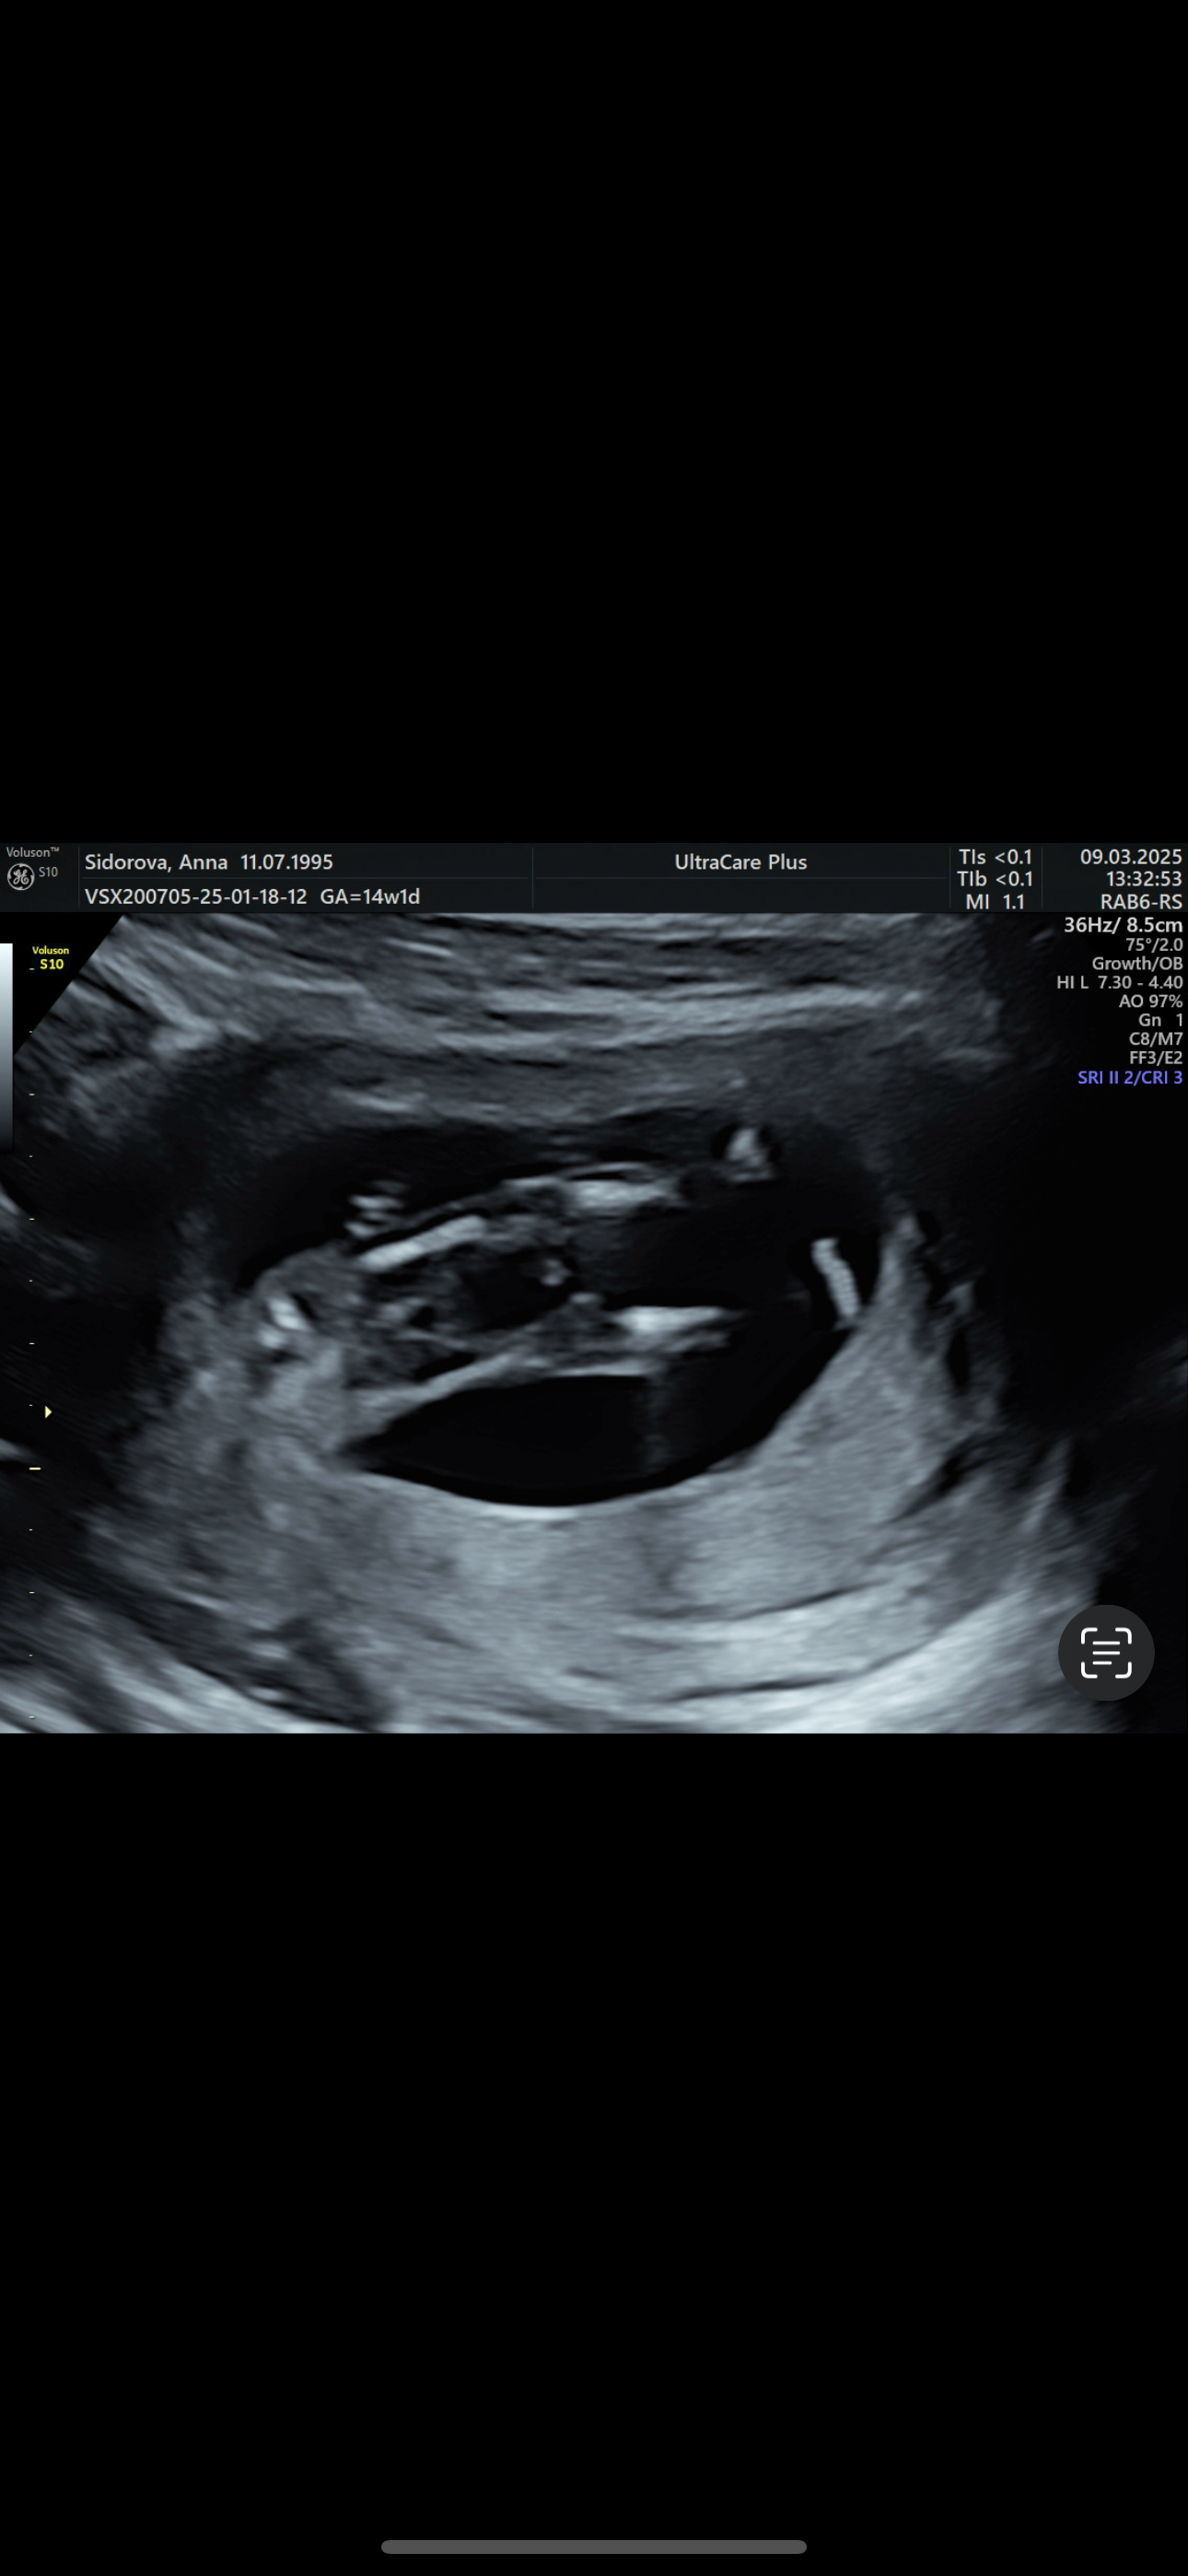

Пол малыша

Девочка по половом бугорку, а точно между ног, это пуповина

Девочка, половой бугорок параллельно в телу. Ни на одном фото мальчиком не выглядит. Снизу на таком сроке неинформативно смотреть, только сбоку.

Скрининг в 13,5 недель в МедЭксперт. Пол двойни❤️💙